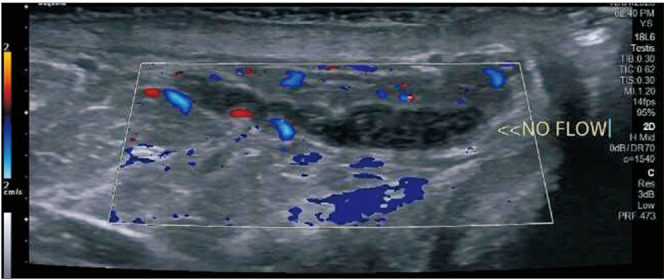

Spontaneous pampiniform venous plexus thrombosis may cause chronic scrotal pain.

自发性阴囊静脉丛血栓可能会导致慢性阴囊疼痛。